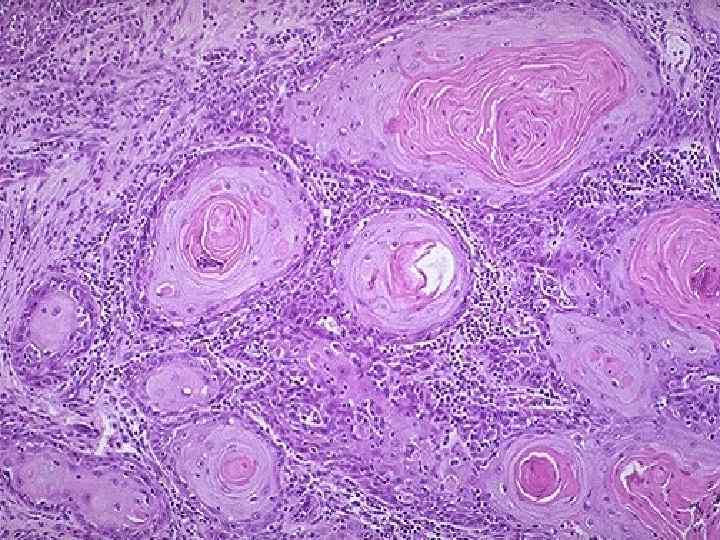

Рак шейки матки n Рост – экзофитный Гистологически – плоскоклеточный рак n